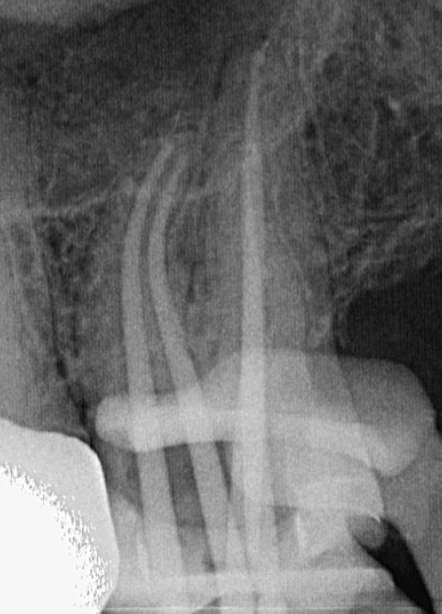

Röntgenologischer Befund:

Das präoperativ angefertigte Röntgenbild (Abbildung 10) zeigt den bereits vom Vorbehandler trepanierten Zahn 27. Die Wurzelfüllung erscheint inhomogen. Das Wurzelfüllmaterial im mesiobukkalen Kanal ist über den röntgenologischen Apex hinaus extendiert und es zeigt sich eine periapikale Osteolyse der mesiobukkalen Wurzel.

Abbildung 10: Präoperative diagnostische Aufnahme

Die Revisionsbehandlung erfolgte in zwei Sitzungen. Nach Anlegen des Kofferdams wurde die provisorische Füllung entfernt und die Zugangskavität gereinigt. Im Anschluss erfolgte die intrakoronale Diagnostik (Abbildung 11). Es zeigte sich bakteriell besiedeltes Wurzelfüllmaterial im mesiobukkalen, distobukkalen und palatinalen Kanal. Das Orifizium des mesiobukkalen Kanals war in palatinaler Richtung erweitert. Die Entfernung eines mesialen Dentinüberhangs mit langschaftigen Rosenbohrern legte das weit nach palatinal verlagerte Orifizium des zweiten mesiobukkalen Kanals frei. Die Entfernung des Wurzelfüllmaterials erfolgte mithilfe von EdgeFile X7 der Größe 25.06, und 17.06 in Crown Down Technik um die Verschleppung von Keimen und bakteriell besiedeltem Wurzelfüllmaterial nach apikal zu reduzieren. Die Erschließung und initiale Aufbereitung des zweiten mesiobukkalen Kanals wurde mithilfe der EdgeFile X7 der Größe 17.04, 17.06 in alternierender Weise wie oben beschrieben durchgeführt. Nach elektrometrischer Bestimmung der Arbeitslänge aller Kanäle wurde die Präparation mit EdgeFile X7 auf voller Arbeitslänge fortgesetzt. Im ersten mesiobukkalen Kanal, distobukkal und palatinal wurde die Aufbereitung mit EdgeFile X7 der Größe 40.06 abgeschlossen, während der zweite mesiobukkal Kanal bis 30.06 aufbereitet wurde (Abbildung 13).

Abbildung 11: Nach Ausarbeiten der primären Zugangskavität; Darstellung des mb2 in der Nähe des palatinalen Kanals

Nach Abschluss der Präparation wurden die Kanäle getrocknet, Kalziumhydroxid auf volle Arbeitslänge eingebracht und der Zahn provisorisch mit einer adhäsiven Kompositfüllung verschlossen. Die Weiterbehandlung fand nach zwei Wochen bei Beschwerdefreiheit statt. Nach erneuter elektrometrischer Kontrolle der Arbeitslänge, Anfertigung einer Masterpointaufnahme (Abbildung 12) und schallaktivierter Abschlussspülung mit 17% EDTA und 6% NaOCl wurden die Kanäle in warm vertikaler Fülltechnik mit biokeramischem Sealer gefüllt (Abbildung 15). Der direkte adhäsive Verschluss der Zugang erfolgte mit einem Bulk Fill Flow Komposit (Abbildung 14).

Abbildung 12: Masterpointaufnahme

Abbildung 13: Kanalsystem nach Aufbereitung

Abbildung 14: Nach Obturation und adhäsivem Verschluss Abbildung 15: Zugangskavität nach Obturation